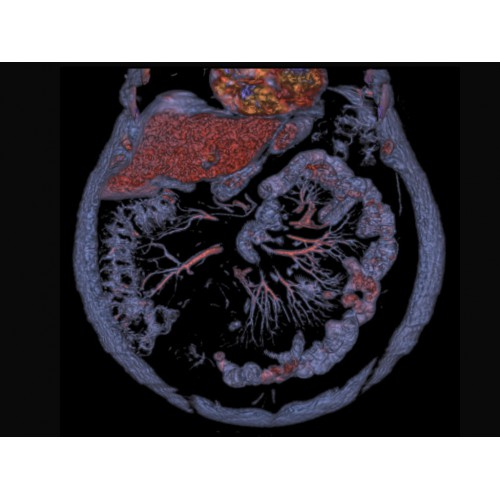

Онкология

• Раннее выявление новообразований и контроль эффективности лечения.

• Планирование лучевой терапии с высокой точностью.